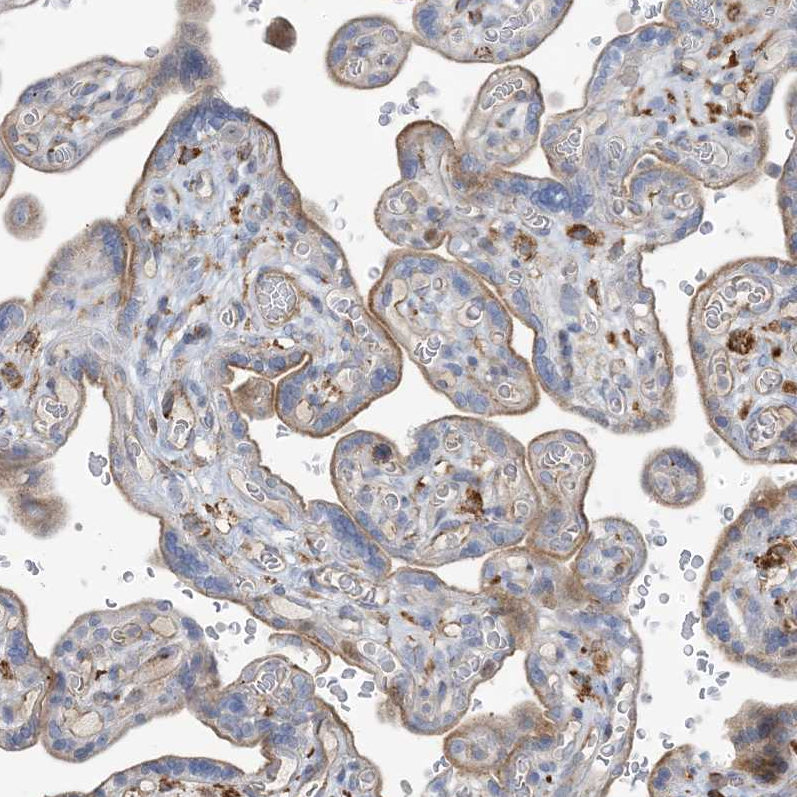

Immunohistochemical staining of human bone marrow shows moderate membranous positivity in hematopoietic cells.